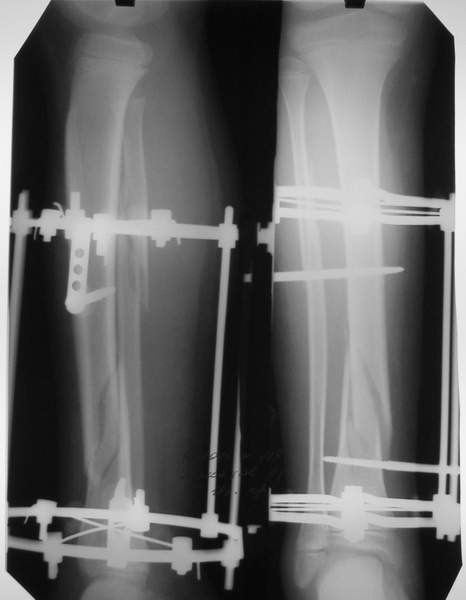

Под рукой прилагаемый пример. Как видите, "стриптиз-аппарат" (шутка проф. З.К.Башурова): 3 кольца-2 кольца-2 полукольца. В случае, который представил Евгений, характер повреждения позволил бы сразу использовать аппарат на основе 2 колец; в крайнем случае прокс. опора м.б. демонтирована сразу после репозиции.

В аттачтах №№ 1 и 2 - примеры, когда 2 кольца не позволили послеоперационно

исправить смещение фрагментов большеберцовой (по ширине и вальгусное).

1

1a